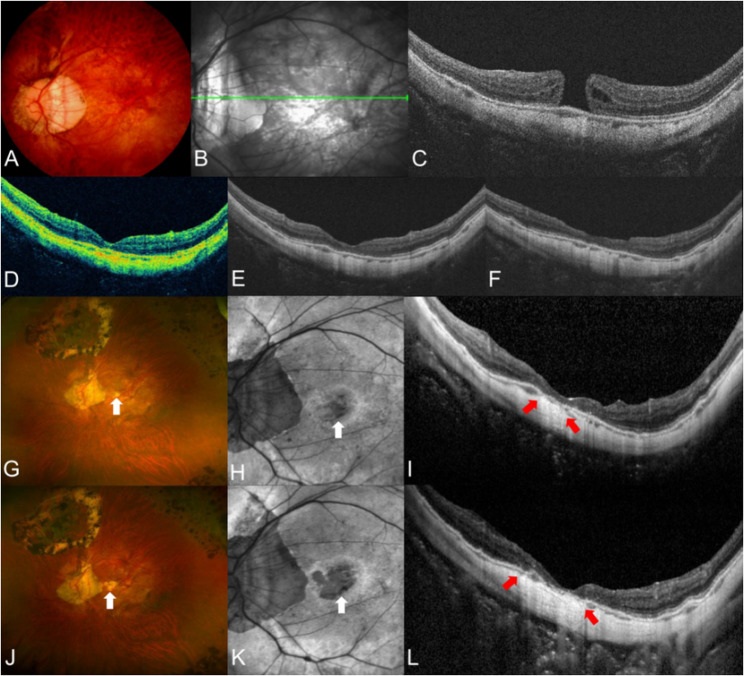

背景:探讨无视网膜裂的高度近视全层黄斑裂孔(FTMH)的临床特点和远期手术效果。方法:回顾性评价高度近视患者行玻璃体切除术联合内限制膜剥离和气体填塞治疗无视网膜裂的FTMH的手术效果。术后检查分别在术后1、3、6和12个月进行,进一步的随访间隔根据医生的判断进行调整。评估与视力和解剖成功相关的临床特征,定义为孔闭合而不发生中央凹萎缩。结果:纳入33只眼(30例),平均随访61.1±48.8个月。31只(93.9%)眼实现了黄斑孔闭合,其中16只(51.6%)眼在随访中出现中央凹萎缩。在整个随访期间,解剖成功眼的视力预后明显优于未解剖成功眼(P≤0.031),术后6个月、12个月和最后一次随访时的视力较基线有显著改善(P = 0.002, P)。结论:高度近视合并视网膜裂的FTMH患者玻璃体切除术后的闭孔率较高。然而,术后中央凹萎缩的发展阻碍了视力的改善。后葡萄肿,最小孔直径较大,轴向长度较长预示预后不良。

Results: Thirty-three eyes (30 patients) were included, and the mean follow-up period was 61.1 ± 48.8 months. Macular hole closure was achieved in 31 (93.9%) eyes, of which 16 (51.6%) developed foveal atrophy during follow-up. Eyes with anatomical success exhibited a significant better visual prognosis than those without during whole follow-up period (P ≤ 0.031), showing a significant postoperative visual improvement from baseline at 6 months, 12 months and final visit (P = 0.002, P < 0.001 and P = 0.013, respectively). Greater minimal macular hole diameter (P = 0.002) and the presence of posterior staphyloma (P = 0.040) were significantly related to anatomical failure, whereas longer axial length was significantly related to poorer final best-corrected visual acuity (P < 0.001).

Conclusions: Hole closure rate after vitrectomy in highly myopic patients with FTMH without retinoschisis was high. However, the postoperative development of foveal atrophy hindered vision improvement. Posterior staphyloma, greater minimal hole diameter, and longer axial length were predictive of poor prognosis.